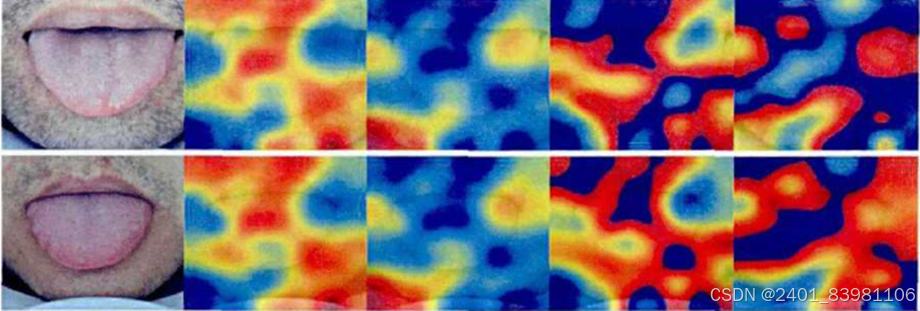

采用VGG时网络优化过程中应用了Dropout策略网络优化策避免过拟合问题但训练样本较少,采集数据困难,训练样本包含舌头外的无关区域等原因,产生的可视化效果并不够完美,仍具有相当大的改进空间

对应的可视化图:

采用h-Unet解决Unet没有全连接层问题(对应可视化图)

采用VGG时网络优化过程中应用了Dropout策略网络优化策避免过拟合问题但训练样本较少,采集数据困难,训练样本包含舌头外的无关区域等原因,产生的可视化效果并不够完美,仍具有相当大的改进空间